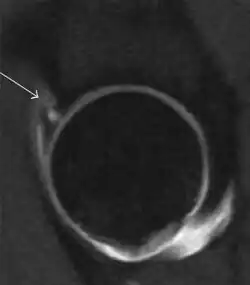

Most of the angles and measurements described in the plain radiograph section can be accurately reproduced on MRI. In addition, the superiority of MRI resolution with intra-articular contrast allows detection of labral and chondral abnormalities that may influence the choice of medical, percutaneous, or surgical management (Figure 9).[1]

Figure 9:

-

Sagittal T1 weighted image showing anterosuperior labral tear.[1] -

Sagittal T1 weighted image showing chondral lesion.[1] -

Sagittal CT-arthrography showing posteroinferior chondral injury.[1] -

Coronal CT-arthrography (d) showing ligamentum teres tear.[1]

MR arthrography has proven superior in accuracy when compared to native MR imaging. It is considered the best technique to assess the labrum. Knowledge of the normal variable morphology of the labrum helps to differentiate tears from normal variants. A triangular shape is most commonly seen in 66% of asymptomatic volunteers, but round, flattened, and absent labra can also be found in asymptomatic populations. MR arthrography has demonstrated sensitivity over 90% and specificity close to 100% in detecting labral tears. Loose bodies are demonstrated as filling defects surrounded by the hyperintense gadolinium.[1]

Association between labral tears and chondral damage has been demonstrated. This underscores the interaction between cartilage and labrum damage in the progression of osteoarthritis. Chondral damage to the posteroinferior part of the acetabulum as a contrecoup lesion occurs in approximately one-third of pincer cases secondary to persistent abutment on the anterior part of the joint leading to a slight posteroinferior subluxation. This is considered a bad prognosis sign.[1]

MR arthrography can also demonstrate ligamentum teres rupture or capsular laxity, which are debated causes of microinstability of the hip. Elongation of the capsule or injury to the iliofemoral ligament or labrum may be secondary to microtrauma in athletes. MR can demonstrate abnormalities in these cases, such as increased joint volume or a ligamentum teres tear (Figure 9).[1]